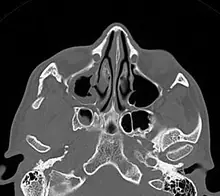

Fracture du plancher de l’orbite